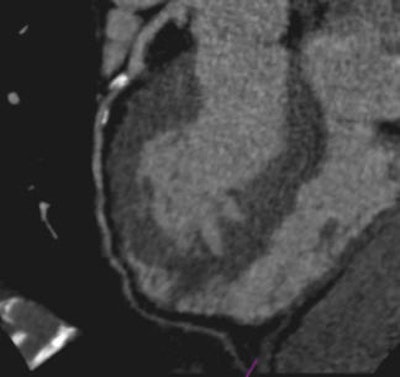

Images of a 65-year-old male patient acquired in dual-source CT high-pitch mode show good enhancement of the coronary arteries down to their distal portions. Top image shows calcified stenosis at the origin of the proximal portion of the left anterior descending (LAD) artery.Bottom image depicts the left circumflex (LCX) artery, and an absence of atherosclerotic lesions. The acquisition consisted of a whole-chest CT angiography exam obtained without beta blockers or electrocardiac gating. All images courtesy of Dr. Martine Rémy-Jardin.Collimation was set thin at 0.6 mm, and protocols for both machines used individually adapted selection of kVp for tubes A and B, at 100 kVp (body weight < 80 kg) or 120 kVp (body weight 80-120 kg). Automatic adjustment was achieved using CareDose (Siemens) with a reference setting of 90 mAs.